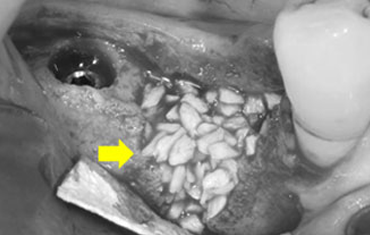

램브란트치과 상인점 뼈이식 후 골조직

윗턱뼈 공기주머니에 뼈이식

치료 전

치료 후